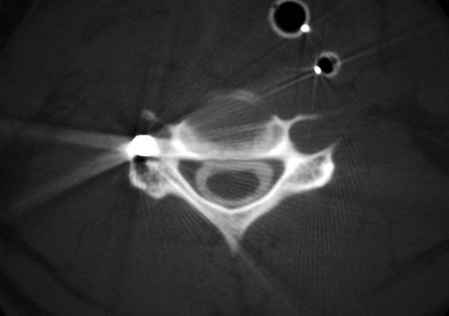

2、 CT掃描

當(dāng)X線片上脊柱受損的情況顯示不清時(shí),行軸位CT掃描可提示骨折的部位,椎管內(nèi)有無骨折片突入或金屬碎片。注意有無椎管內(nèi)血腫。

脊髓火器傷